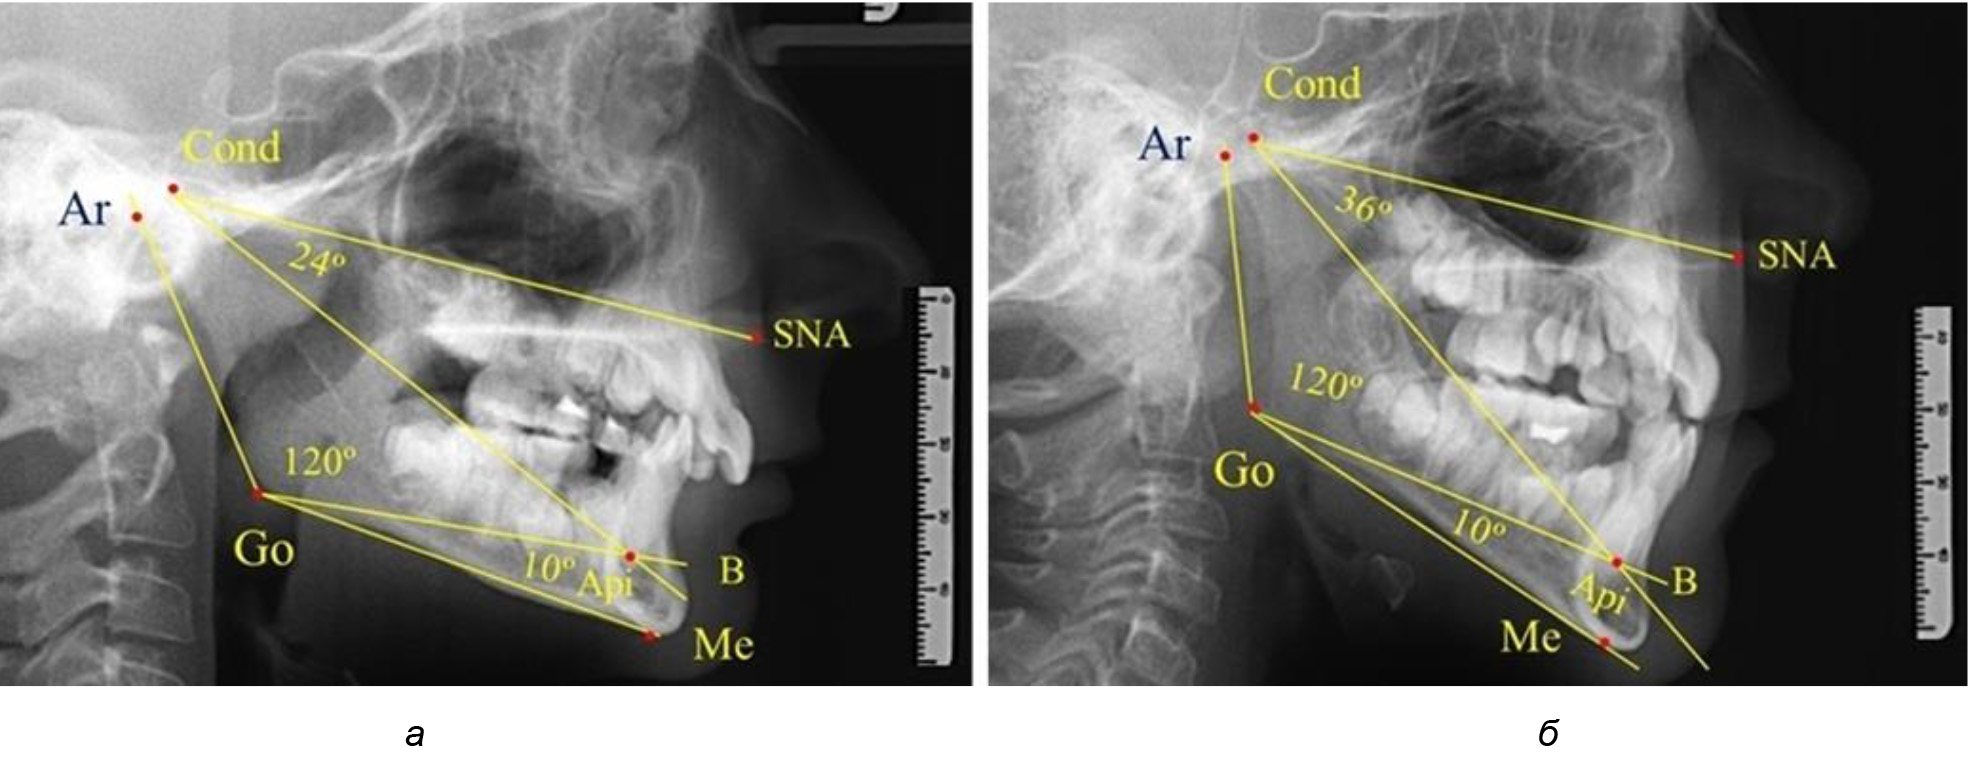

Таким образом, в периоде молочного прикуса с оптимальными окклюзионными соотношениями, несмотря на линейные размеры в вертикальном и сагиттальном направлении, которые, безусловно, меньше параметров взрослых людей, величина основного угла гнатической части лица SNA-Cond-Api соответствовала параметрам людей с полностью сформированным физиологическим прикусом постоянных зубов. Анализируя данные рентгенограмм детей в периоде сменного прикуса, отмечено, что величина основного угла гнатической части лица SNA-Cond-Api, так же как в молочном и постоянном прикусе, в норме составляла от 28 до 32°. В то же время угол нижней челюсти и его составляющие отличались вариабельностью параметров при различных показателях нижнечелюстного угла. Достоверных различий угла гнатической части после смены нижних медиальных резцов и прорезывания первых постоянных моляров (4 ребенка) не было; происходил очередной этап подъема высоты прикуса и увеличение линейных размеров костей гнатической части, однако угловые параметры были относительно стабильны. После смены всех резцов и замены первых молочных моляров первыми премолярами (6 человек) увеличивались линейные размеры при сохранившихся угловых показателях гнатической части лица (рис. 5).

Рис. 5. Варианты ТРГ после прорезывания ППМ и нижних резцов (а), всех резцов и первых премоляров (б)

Таким образом, в период сменного прикуса с оптимальными окклюзионными соотношениями, несмотря на увеличение линейных размеров в вертикальном и сагиттальном направлении, по сравнению с прикусом молочных зубов, величина основного угла гнатической части лица SNA-Cond-Api соответствовала показателям как постоянного, так и молочного прикуса с физиологическими окклюзионными соотношениями.

После смены всех молочных зубов (анализ 9 ТРГ) и после прорезывания вторых постоянных моляров (7 человек) происходил очередной этап подъема высоты прикуса с увеличением размеров костей гнатической части лица. Однако величина основного угла гнатической части лица SNA-Cond-Api, так же как в молочном и сменном прикусе, в норме составляла (30,02 ± 1,25)°, что не имело достоверных различий (р ˃ 0,05) с аналогичным параметром, анализируемом в других группах исследования. Угол нижней челюсти и его составляющие отличались вариабельностью параметров при различных показателях нижнечелюстного угла (рис. 6).